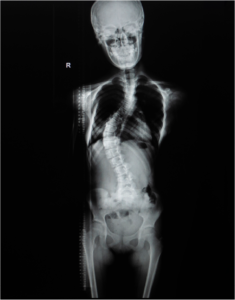

Scoliosis

Scoliosis is a condition characterized by abnormal curvature of the spine causing a deviation to one side. It causes a physical deformity making the spine…